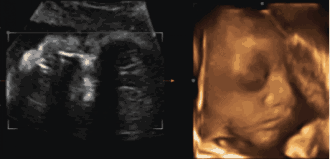

为了提前探寻这一“真相”

我们可以通过一个特别的仪式

在影像中让宝宝与爸爸妈妈提前相遇

感受宝宝与父母奇妙的连接

这一切,只需要选择四维彩超就可以啦